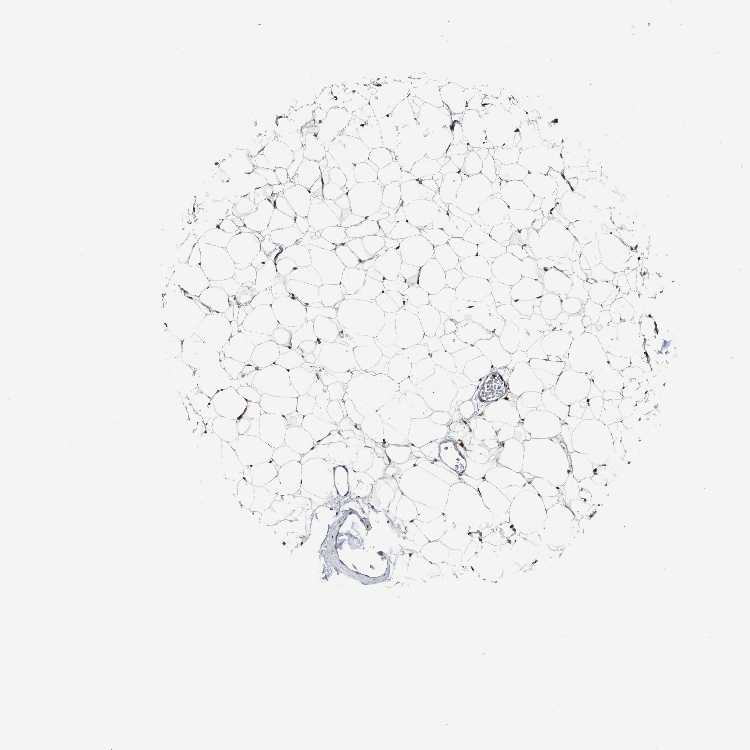

SOFT TISSUE 1 - Antibody stainingi

Antibody staining in the annotated cell types in the current human tissue is reported as not detected, low, medium, or high, based on conventional immunohistochemistry profiling in selected tissues. This score is based on the combination of the staining intensity and fraction of stained cells.

Each image is clickable and will lead to virtual microscopy that enables deeper exploration of all samples and also displays staining intensity scores, fraction scores and subcellular localization as well as patient and tissue information for each sample.

Antibody HPA020514

Chondrocytes Medium

Fibroblasts High

Peripheral nerve Not detected